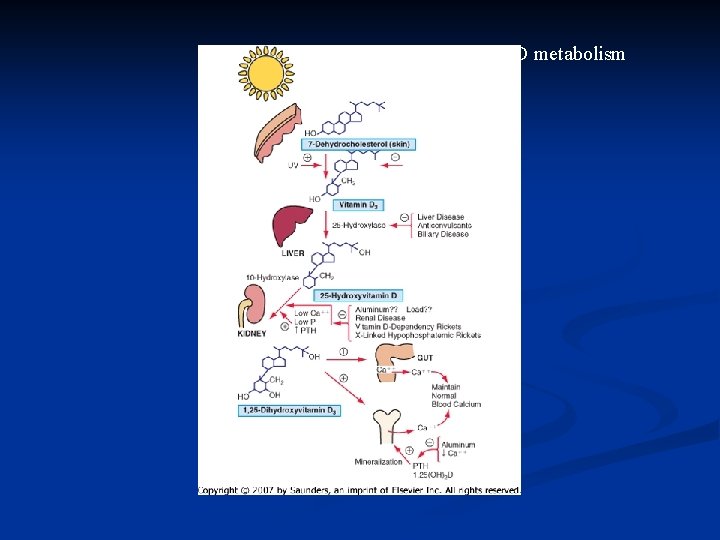

Biochemistry of Vitamin D 3 – Brief Review Vitamin D 3 (cholecalciferol) is synthesized in the skin, with UV light, from 7 -dehydrocholesterol n Vitamin D 3 is hydroxylated twice – first in the liver, to 25 hydroxycholecalciferol, then in the kidney, to 1, 25 dihydroxycholecalciferol, the most potent form of Vitamin D n

Vitamin D metabolism

Vitamin D Metabolism

Vitamin D Deficiency n Secondary to Insufficient sun exposure n Malabsorption, Malnutrition n Liver disease n Renal disease, nephrotic syndrome n Anticonvulsants (generics Phenytoin, Carbamazepine, Valproate, Phenobarbital) can inhibit hepatic hydroxylation of Vitamin D n

Chronic liver disease Cirrhosis reduces 25 -hydroxylation of vitamin D n Biliary obstruction: n prevents absorption of fat soluble vit D n Interrupts its enterohepatic circulation n

Chronic renal failure n n n Reduces 1 hydroxylation of 25 hydroxy vitamin D leads to low concentration of 1, 25 -di hydroxy vitamin D Consequently impair calcium absorption from the gut Renal osteodystrophy n n Osteitis fibrosa cystica due to long standing secondary hyperparathyroidism When GFR falls below 30 ml/min/1. 73 m 2 n n Impaired growth Osteitis fibrosa results n n n Sub-periosteal resorption at middle and distal phalanges Bone pain Muscle weakness